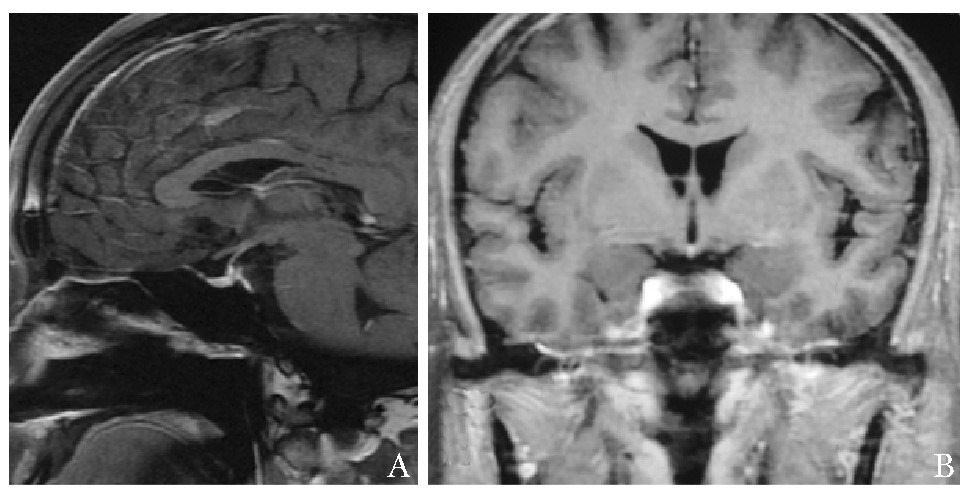

• 摘要: 建立正确的临床思维是提升临床能力的核心和根本,是医学教育的重点及难点。与常见病不同,垂体疾病作为一种罕见病,其临床思维具有其独特性。本文以一例下丘脑垂体多发占位为例,从资料搜集、逻辑推理、循证教学、多科讨论、基础医学研究等方面总结罕见病诊断思维特点,以期提高临床医师的工作效率,并为垂体疾病的临床思维训练提供相关经验。

Abstract: Establishing correct clinical thinking is the core and foundation of improving doctors' clinical ability as well as the key and difficult point of medical education. Different from common diseases, clinical thinking about pituitary diseases has its unique characteristics as a rare disease. Taking a case of Hypothalamic and pituitary mass as an example, this paper summarized the characteristics of diagnosis thinking of rare diseases from the aspects of data collection, logical reasoning, evidence-based teaching, multiple disciplinary teams, and basic medical research, to improve the efficiency of physicians and provide experience for the training of clinical thinking about pituitary diseases.